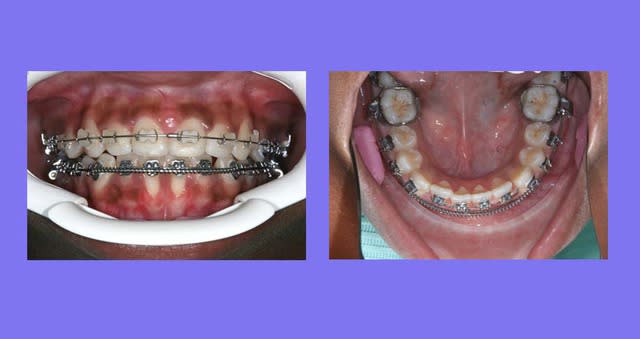

il m'a été reproché de ne pas montrer le cas en entier et de ne pas expliquer comment j’avais traité

Voici le cas depuis le début, traité avec mes Bk. modifiés qui permettent de travailler en passif en début de traitement, en inter-actif au milieu de traitement, avec ou sans les ressorts de Root, et parfois en friction forte en fin de traitement pour les finitions

C’est un cas ancien ou je ne faisais pas assez de photos et ou j’essayais différentes marques de Bk.

soyez indulgent

Reprise du cas au départ

1°) Q.H. Sup pendant 6 mois, désolé, pas de photos

2°) Appareillage MB. Sup et 2 mois après Inf., avec mes Bk. modifiés en position Damon

On peut observer un décalage des points inter-incisifs et des rotations des Inc. Inf.

Voir Photo

@ suivre Bjc.